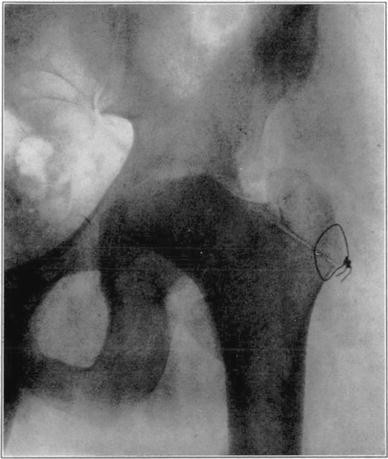

Case 1. Bony ankylosis following pyogenic arthritis.

Case 1. Twenty days after arthroplasty.

Case 1. Thirty-six days after arthroplasty. Beginning reduction in density in base of neck and shaft. No change in head.

Case 1. One hundred and fifty-one days after operation. Density of necrotic head unchanged but shaft and pelvis show atrophy of disuse.